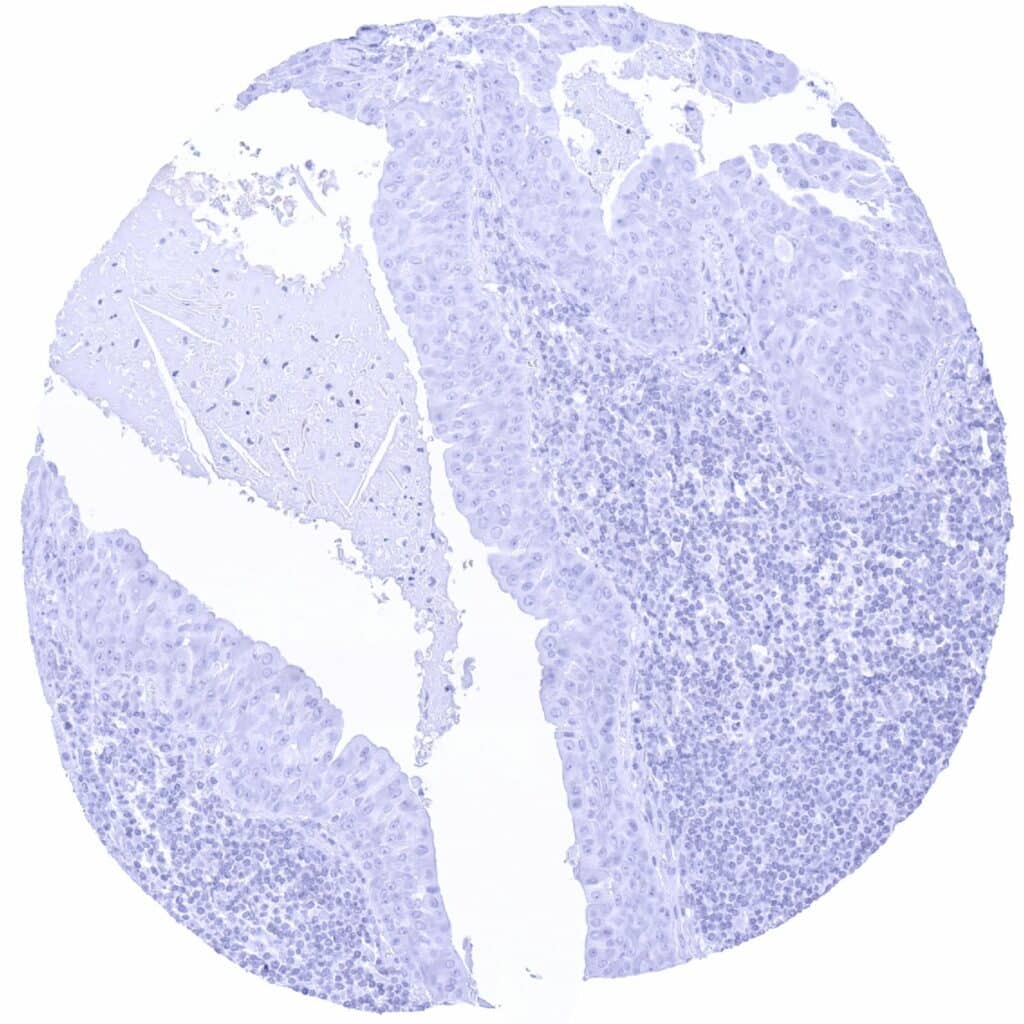

PAX6 antibody [MSVA-706M] HistoMAXTM

Lymph node – PAX6 negative diffuse large B-cell lymphoma